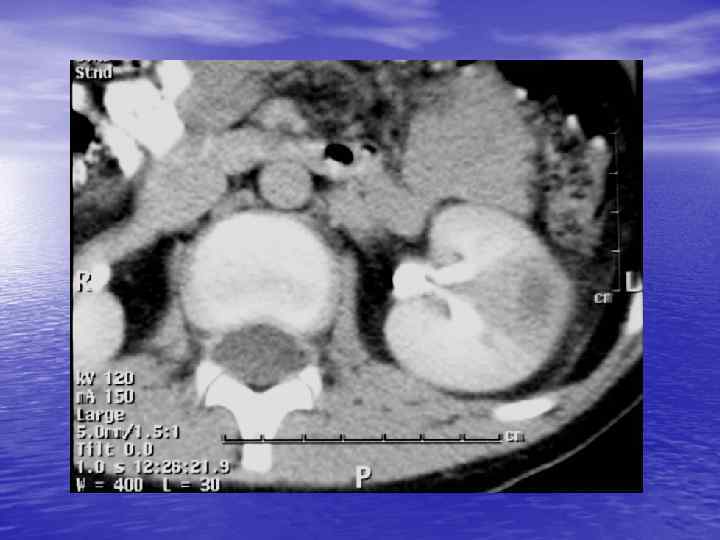

Анализ изображения: üструктурный (анатомический) - оценка морфологии üденситометрический - оценка плотности ткани

Структурный анализ Оценка основных макроскопических признаков: - положение - форма - размеры - характер контуров и структур патологически измененных участков

Денситометрический анализ Определение основных видов патологических образований: - обызвествленных - мягкотканных - жидкостных - жиросодержащих - воздухсодержащих

Денситометрия